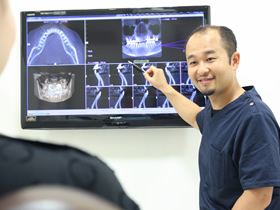

そこで当院では、画像分析ソフトを使用して綿密な詳細分析を行い、

できるだけ歯を抜かない矯正治療を心がけています。

この結果をもとにコンピューターの画像分析ソフトを用いて詳細な分析を行い最適な治療計画を立案いたします。